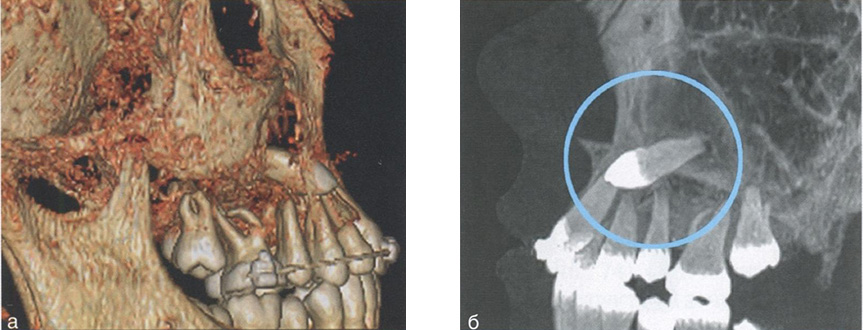

2) положение ретинированных и дистопированных зубов, а также сверхкомплектных зубов (рис. 77);

Оценка положения ретинированного зуба

Рис. 77. Оценка положения ретинированного зуба 2.3 на компьютерных томограммах: а — окно объемного рендеринга; б — окно мультипланарной реконструкции